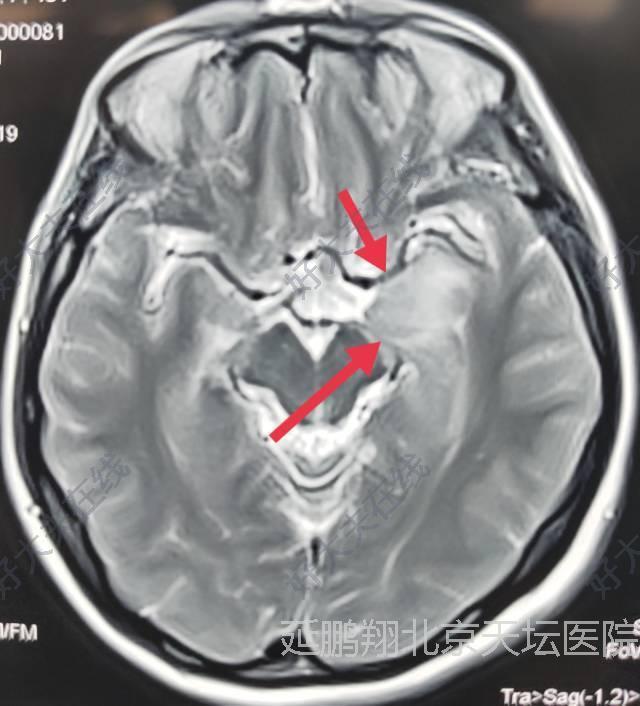

女性,48岁。发作性心悸,心烦,头晕11月。CT和MRI显示左侧鞍旁脑膜瘤,与海棉窦及颈内动脉及大脑中动脉关系密切。

术后病人恢复顺利,睡眠,进食,精神状态,行走均正常。常规复查核磁,显示肿瘤消失。